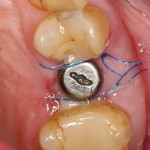

Что мы и сделали. Удалили зуб:

Критически важно провести удаление аккуратно, чтобы не разрушить и без того тонкие стенки альвеолы. Вообще, в хронометраже операции немедленной имплантации удаление зуба занимает 75% времени, это наиболее сложная и деликатная часть вмешательства.

Затем лунка зуба адаптируется, в нее устанавливается имплантат, в данном случае Friadent XiVE диаметром 4.5 и длиной 13 мм:

Если не предполагается немедленная нагрузка (изготовление коронки на имплантат), первичная стабильность не является обязательной. Тем более, нельзя пытаться ее достичь, меняя положение и, особенно, погружение импланта. Если есть опасения, можно закрыть имплантат заглушкой, а саму лунку герметично ушить, используя свободный слизистотканный аутотрансплантат или (что разумнее) коллагеновую матрицу Mucograft Seal. Про последнюю обязательно расскажу вам, как только наберу достаточное количество клинических примеров.

Но в данном случае стабильность хорошая, на имплантат фиксируем формирователь десны, накладываем швы:

Еще один важный момент. Не нужно пытаться стянуть рану и добиваться плотного прилегания десны к формирователю. Любое натяжение слизистой оболочки ведет к ее изменению (прикрепленная десна становится подвижной), а процессы атрофии костной ткани ускоряются. Чем меньше тянем и перемещаем — тем лучше. Поэтому вполне разумно оставить вокруг формирователя открытую рану шириной 0.5-1.5 мм, она нормально заживет вторичным натяжением.